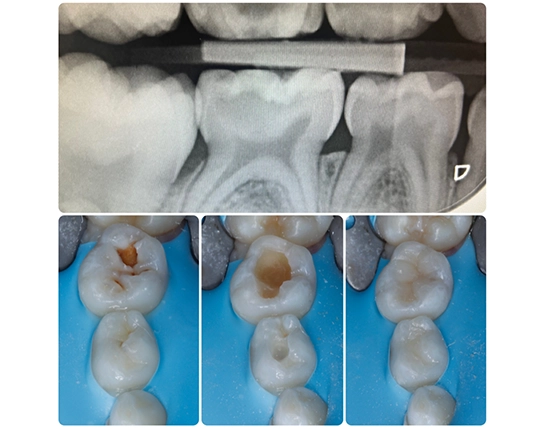

Figure 7

Images from a bitewing radiograph and preparations and final restorations on deciduous molars during the restorative phase.